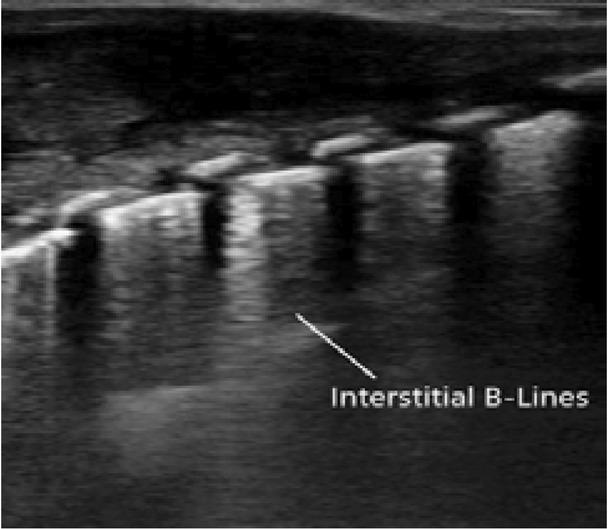

Fig. 3